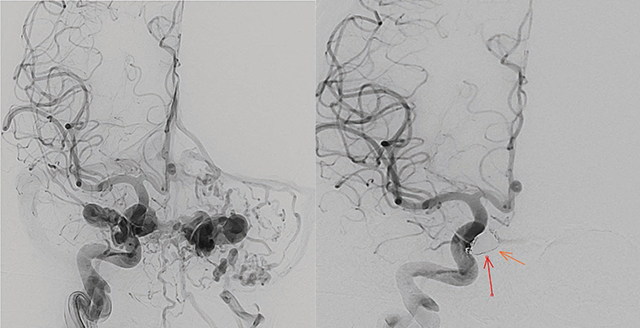

Carotid-cavernous fistulas (CCFs) are abnormal connections between the carotid arteries and the cavernous sinus, posing significant neuro-ophthalmologic risks. This report presents a rare case of bilateral post-traumatic CCFs, focusing on clinical presentation, diagnosis, and management. Symptoms mimic conjunctivitis, causing diplopia, exophthalmos, and ophthalmoplegia. Diagnosis relied on computed tomography, magnetic resonance angiography, and digital subtraction angiography. Management involved transarterial embolization with coils, achieving successful outcomes. This highlights the importance of timely intervention and comprehensive imaging to prevent complications. Teaching point: This case report details a rare instance of bilateral post-traumatic carotid-cavernous fistulas, emphasizing clinical presentation, diagnostic evaluation, and management.

颈动脉海绵窦瘘(CCFs)是颈动脉和海绵窦之间的异常连接,对神经眼科构成重大风险。本报告介绍了一例罕见的双侧外伤后 CCF 病例,重点阐述了临床表现、诊断和处理方法。症状类似结膜炎,导致复视、眼球外翻和眼肌麻痹。诊断主要依靠计算机断层扫描、磁共振血管造影和数字减影血管造影。治疗包括使用线圈进行经动脉栓塞,取得了成功。这凸显了及时干预和全面成像对预防并发症的重要性。教学要点:本病例报告详细介绍了一个罕见的双侧创伤后颈动脉海绵瘘病例,强调了临床表现、诊断评估和处理方法。